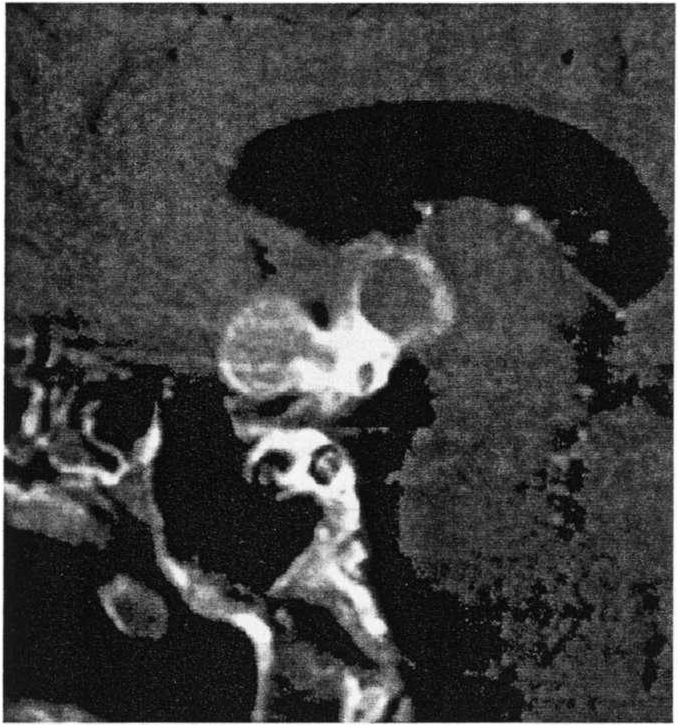

A 9-year-old girl presented to her pediatrician with

headaches and a bitemporal field cut. Her MRI is depicted below. Which of the following would be true

regarding the endocrine outcome after surgical resection of this tumor?

B. The most serious and disabling problem is the development of obesity, which occurs in about 50% of these patients after surgery

A significant number of children with craniopharyngiomas will have a significant endocrine abnormality after

surgery, which is quite predictable. The most serious complication appears to be obesity, which develops in about 50% of patients. These patients are unable to control their appetite secondary to damage to the hypothalamic satiety center. Growth hormone may benefit these patients, as it appears to reduce body fat and increase lean body mass. Nearly 50% of patients will require GH-replacement therapy. Diabetes insipidus occurs in about 90% of patients and is often permanent. Moreover, about 90% of patients will require hydrocortisone and thyroid replacement therapy after surgery